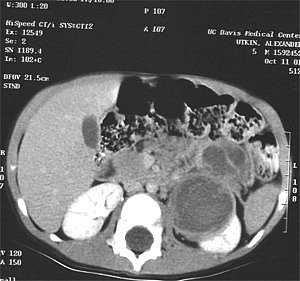

Эхография и РКТ позволяет значительно точнее определить анатомо-топографические и, в какой-то степени, морфологические характеристики нефробластомы (Рис. 1, 2). У всех наших пациентов опухоль была представлена объёмным образованием в виде солитарных масс преимущественно неправильной формы (95,2%). В области опухолевого узла контур почки был выпуклым (14,3%). В 50% обнаруживалась экзофитная зона с фрагментарно выраженной капсулой (71,4%). Эхографическая картина и изображение поражённой почки на РКТ были весьма схожи. Опухоль выглядела как негомогенная структура с преобладанием гиподенситивных очагов (90,5%). Эхографически кальцинаты при нефробластоме выглядят как редкие небольшие высокоинтенсивные сигналы и обнаруживались редко.

Рис. 1. Рентгеновская компьютерная томограмма опухоли почки. Чётко видно, как часть почки замещена опухолевой массой.